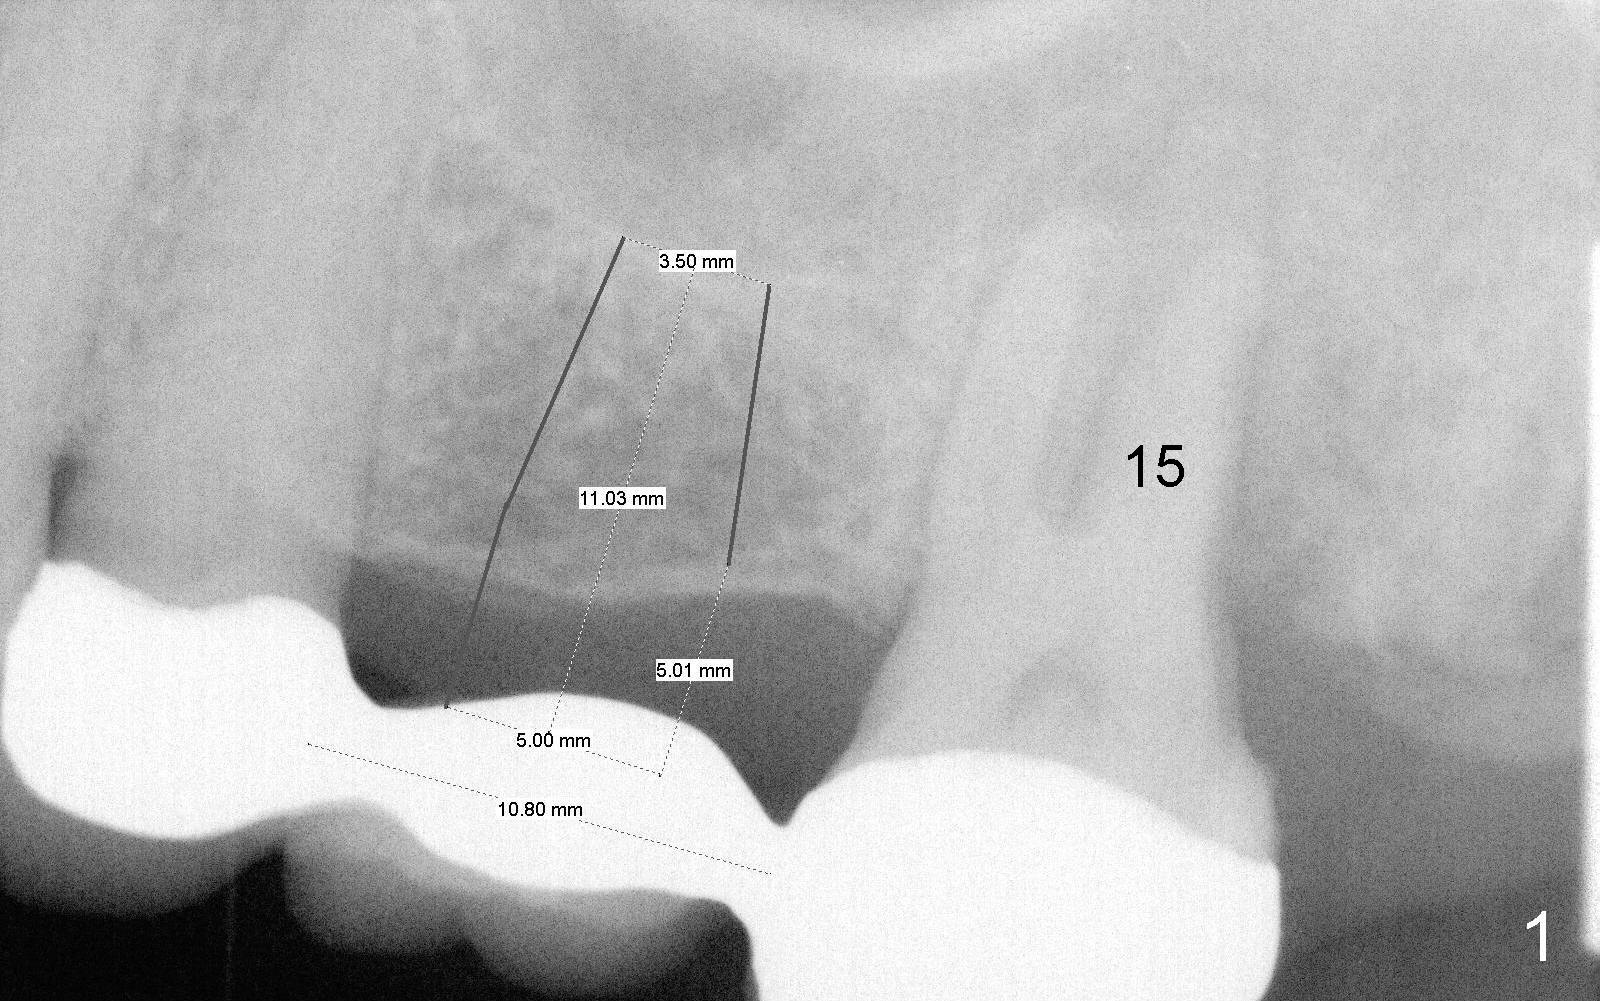

A 65-year-old lady has a failing FPD in the upper left quadrant (Fig.1). After the posterior abutment (#15) is extracted, an implant is planned at the site of #14 (5x11 mm). The bone width and density are expected to be low, considering the long term loss of the tooth.